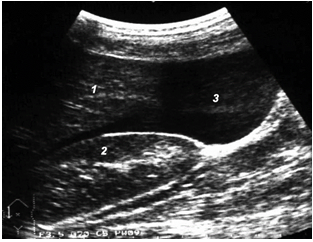

При «среднем» гемоперитонеуме, помимо малого таза, кровь эхографически определяется в печеночно-почечном кармане, латеральных каналах, периспленическом пространстве, ее объем колеблется от 7,6 до 25,8 мл/кг массы тела (рис. 12).

Рис. 12. «Средний» гемоперитонеум: 1 – печень; 2 – почка; 3 – кровь.